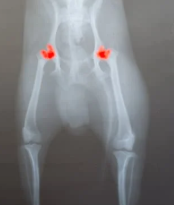

4) 진단 방법

보통 동물병원에서는 엑스레이(X-ray), 초음파, MRI 등을 통해 관절 구조를 확인합니다. 특히 전신마취 후 촬영하는 방사선 사진이 확진에 많이 활용됩니다.

강아지 고관절 이형성증은 말 그대로 고관절이 정상적으로 발달하지 못하고 불완전하게 형성되는 질환입니다. 고관절은 골반과 대퇴골(허벅지 뼈)을 이어주는 중요한 관절인데, 성장 과정에서 이 부분이 제대로 맞물리지 않으면 관절이 느슨해지고 마찰이 생기면서 통증과 변형으로 이어집니다.